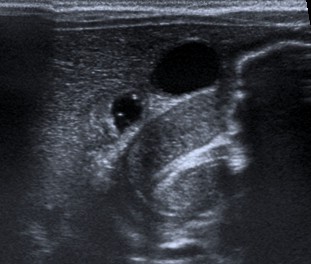

Las sondas que se deben utilizar son las lineales de entre 7-15 MHz (sondas de alta frecuencia). Estas sondas permiten identificar todas las capas de las pared del píloro. A la hora de realizar la prueba es mejor que el estómago se encuentre con poco contenido gástrico. Si el estómago esta lleno de gas se debe poner al paciente en posición oblicua anterior derecha, permitiendo que el líquido gástrico se deposite en el antro por efecto de la gravedad. Un truco es tratar de identificar en primer lugar la vesícula biliar, el píloro suele encontrarse adyacente a la misma.

El signo el doble rail se debe a que la mucosa comprimida presenta múltiples acúmulos líneales de líquido: se ven bandas de líquido hipoecogénicas con bandas hiperecogénicas tanto en visión longitudinal como transversal. En la sección transversal es típico observar la imagen en Donut o anillo hipoecoico heterogéneo con un centro hiperecogénico: el anillo hipoecogénico corresponde a la muscular engrosada, mientras que el centro hiperecogénico corresponder a la superficie mucosa redundante y edematosa.